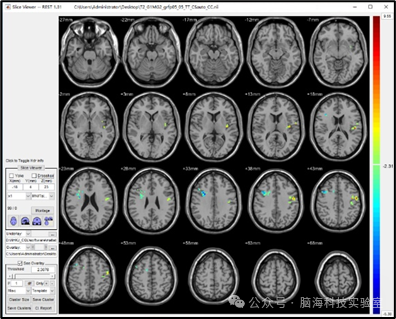

此时,t值为正,表示该区域病人组的脑活动大于正常人组;t值为负,则表示病人组的脑活动小于正常人组。因此,在判断某个差异脑区是否显著降低时,应优先观察该脑区峰值(peak点)t值的正负。如下图RESTplus截图所示:

图片